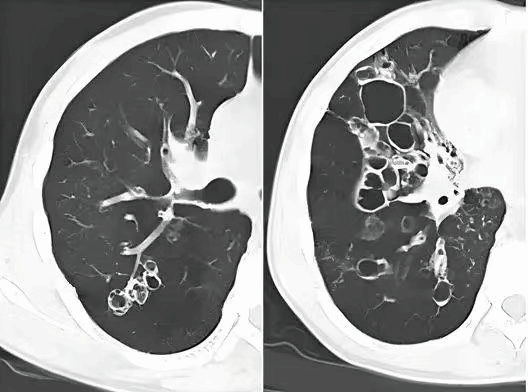

胸部CT检查:高分辨CT(HRCT)可在横断面上清楚地显示扩张的支气管,由于无创、易重复和易接受的特点,已成为支气管扩张的主要诊断方法。